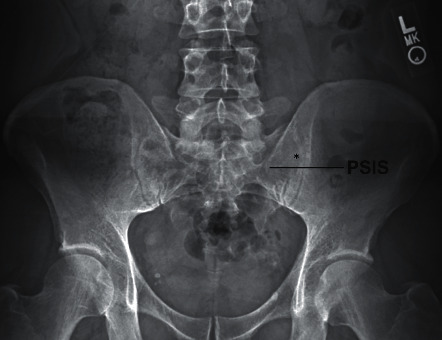

AP fluoroscopic view of the sacroiliac joint. The joint line is identified between the sacrum and ilium. Note the overlapping cortical margins that must be separated with oblique angulation.

2. Fluoroscopic guidance: Use AP or oblique views to visualize the SI joint — the inferior aspect of the joint is the typical entry point

4. Target: Inferior aspect of the SI joint under fluoroscopy

• Apply 10-25 degrees of cephalad tilt so the inferior joint projects just above the superior pubic ramus; this separates posterior from anterior joint planes vertically

• Obtain an adjusted AP view (typically 5-20 degrees contralateral oblique) to superimpose the anterior and posterior joint margins at the caudal third